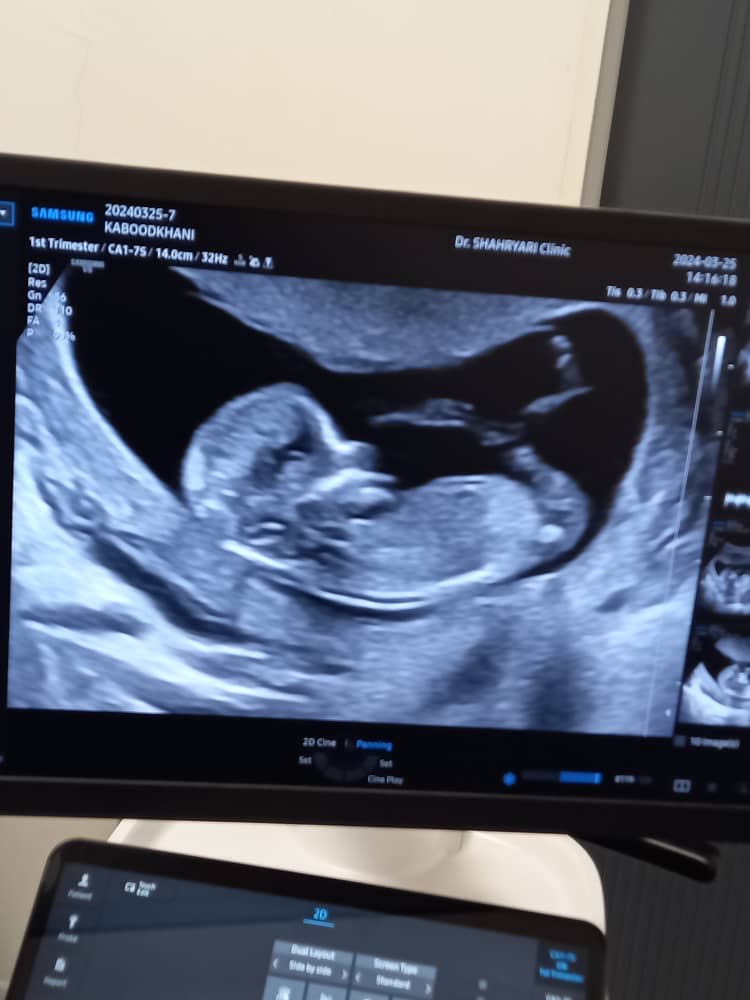

رفقا بیاین جنسیت نینی منو حدس بزنین عکسو اول میزارم

۱۲ هفته و ۳ روز رفته بودم گفته اخر ۱۴ هفته بیا برا جنسیت

الان ۱۳ هفته و دو روزم

ب نظرت بچم چیه؟

نمیدونم عزیزم بنظرم پسره چطور دکتر نفهمیده

گفت کوچیکه اخر ۱۴ هفته بیا برا جنسیت